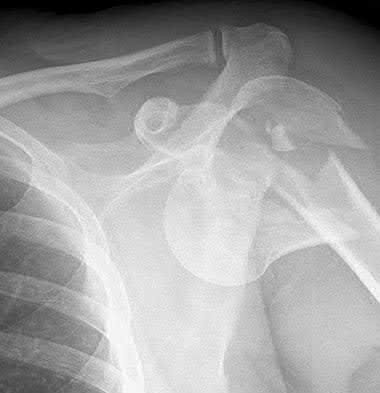

A 70-year-old woman falls down a flight of stairs and sustains the injury shown in Figures A and B to her dominant upper extremity. She lives alone and has no other medical history. Which of the following surgical options is best to minimize complications for this fracture pattern?

This patient has a complex proximal humerus fracture with metaphyseal comminution and poor bone stock. Cemented reverse total shoulder arthroplasty (rTSA) using a long stem prosthesis and tuberosity repair is indicated.

Proximal humerus fragility fractures are hard to treat because of comminution and poor bone stock. AVN is common with glenohumeral fracture-dislocation. Hemiarthroplasty (and standard total shoulder arthroplasty, TSA) is unreliable because of dependence on tuberosity healing. rTSA is recommended for fractures in patients >70 years with severely comminuted fractures, high likelihood of head AVN, and poor tuberosity bone quality (osteoporosis or comminution).

Bufquin et al. retrospectively reviewed the use of rTSA for treatment of 43 patients with 3- and 4-part proximal humerus fractures. They found satisfactory elevation (97°), ER in abduction (30°), constant scores (44) and modified Constant scores (66%). Complications included calcification (90%), tuberosity displacement (53%) and scapular notching (25%). They concluded that rTSA was a good procedure because it provides pain relief and easier functional recovery in spite of failed tuberosity healing.

Anakwenze et al. systematically reviewed acute proximal humerus fractures. Frequency weighted range of motion was flexion 122°, abduction 97°, ER at neutral 18°. Tuberosity repair yielded higher ER compared to no repair.

Scapular notching was the most common complication (32%). They concluded that rTSA patients tended to be elderly women with 4-part fractures, had good pain control but residual dysfunction.

Jobin et al. reviewed rTSA for management of proximal humerus 3- and 4-part fractures. They note >50% of cases have tuberosity resorption. They recommend repairing the greater tuberosity to restore infraspinatus/teres minor function which improves external rotation strength. Greater tuberosity malunion is not a result of secondary displacement, but rather, from intraoperative malreduction. Lesser tuberosity repair should be performed if there is significant bone loss or intraoperative anterior instability.

Figures A and B are AP radiograph and 3D reformatted CT scan showing comminuted proximal humerus fracture dislocation. Illustration A shows rTSA performed with distal cementation of a long stem prosthesis and cerclage fixation of the proximal shaft and the tuberosity fragments.